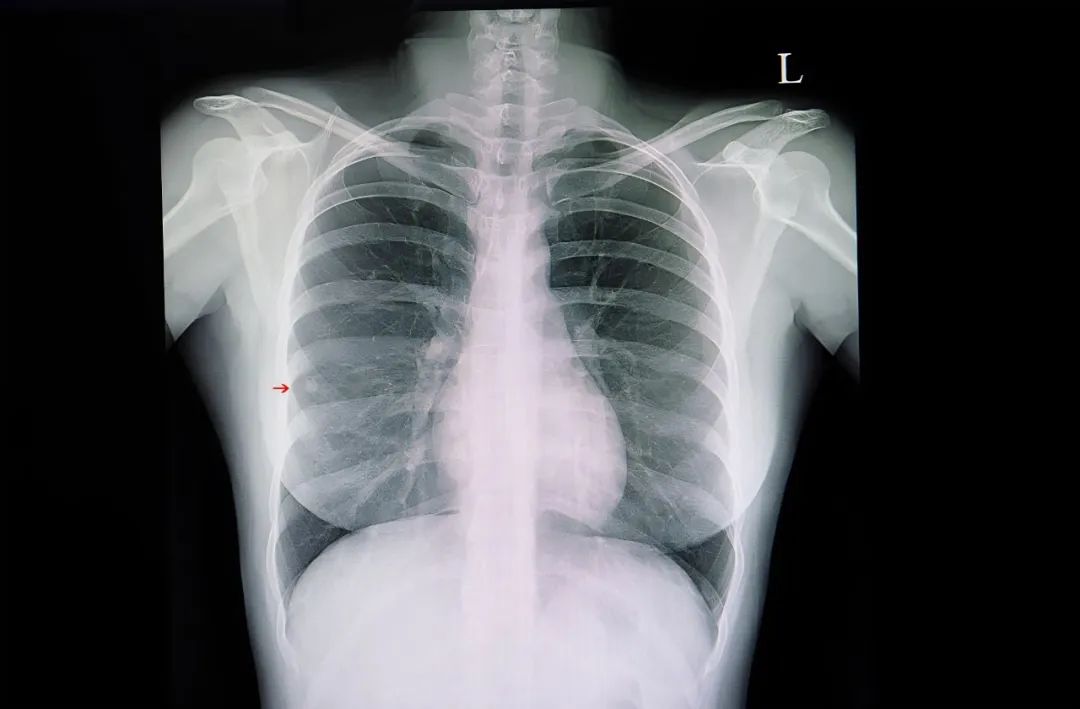

最近幾年,“肺結節”突然出現在很多人的體檢報告中。微小結節、實性結節、磨玻璃結節……這些字眼不免讓人擔憂:它會不會惡化?是否需要立馬切掉?

國內外資料顯示,首次胸部CT掃描篩出的肺小結節,95%以上是良性,但有不少被手術切除了,目前全國各地醫院都存在肺小結節過度診療的現象。

影像學報告往往顯示“斑片樣改變”“磨玻璃密度影”或“形態較規則、邊緣較光滑、境界較清楚”,可出現在甲狀腺、胸膜、肺部、淋巴、腎動脈等部位。

通常,實性小結節的惡性幾率最小,混合性磨玻璃結節惡性率較高,大於8毫米的實性結節、大於6毫米的混合磨玻璃結節均屬於高危結節,需定期複查。

若隨訪發現結節邊緣不規則,分葉、毛刺、胸膜牽拉、含氣細支氣管徵和小泡徵、偏心厚壁空洞等,要考慮臨牀干預。